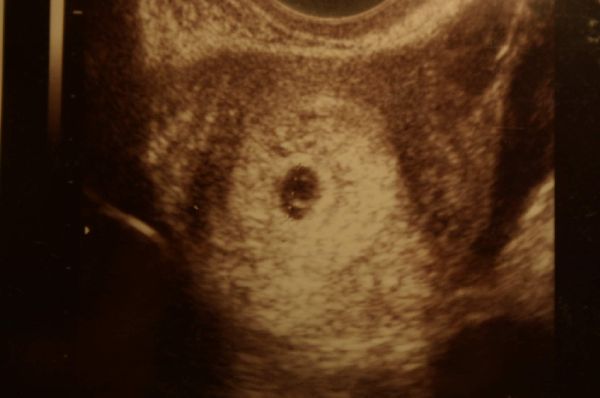

Máté BMC-s baba, 2. inszemmel sikerült.

5 évet vártunk rá (először vártunk, utána saját doki, majd itteni meddőségi doki, és végül BMC). Ahhoz képest, h először lombikot akartak, csak én kikönyörögtem 3 inszemet, jól összejött.

Pocaklakónk meglepetésbaba. Csak úgy jött. Máté még szopott/szopik, nem készültünk rá, csak voltak alkalmak, amikor elengedtük magunkat.